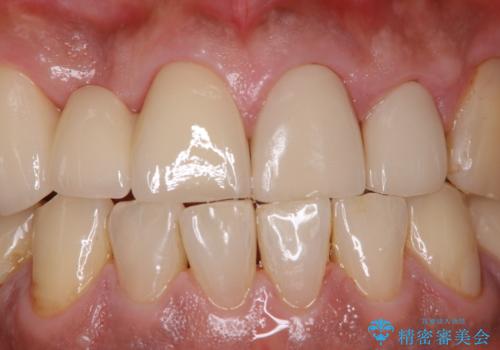

- イベントがあるため、なるべく綺麗にしたいとのことで来院されました。PMTC60分コースを行いました。

またPMTCを行うことで、ご自身本来の歯の色になり自然な明るさになります。

口元が自然な明るさになることで、より清潔感のある印象になるため行事やイベント前などにもPMTCを行うはおすすめです。